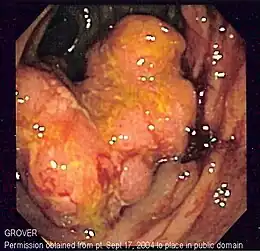

- Colonoscopie : c'est l'examen de référence. Une sonde (long flexible enrobé de plastique) est insérée par l'anus puis glissée peu à peu dans l'intestin. Il permet d'observer la muqueuse et de faire des prélèvements ; si l'on constate un polype, celui-ci est enlevé entièrement et sera analysé au laboratoire par histologie, et son exérèse diminue beaucoup le risque de cancer. La sigmoïdoscopie, un examen plus rapide et moins complet, utilise une courte sonde semi-rigide, qui permet l'exploration du rectum et du colon sigmoïde.

On trouve le plus souvent dans l'intestin des adénomes (= polypes adénomateux). Considéré comme bénin, le polype risque d'évoluer vers un cancer si on le laisse en place, s'il est gros (plus d'un centimètre de diamètre), et/ou s'il est villeux (=avec des villosités). Les petits polypes et les polypes tubulaires présentent moins de risques. On trouve aussi des polypes hyperplasiques, considérés comme pratiquement sans risque. Enfin on trouve dans les colons des adénocarcinomes, qui sont les véritables cancers, dont les cellules dysplasiques franchissent la lamina propria. Ce premier stade de l'invasion peut évoluer pour s'étendre à d'autres organes et conduire à l'apparition de métastases, hépatiques le plus souvent, qui provoquent la mort plus fréquemment que la tumeur initiale.